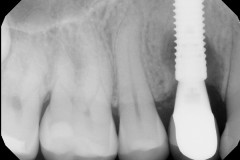

This mouth had recession on just one tooth with very little bone to support the tooth. The area needed support and thickness. The tissue was placed and the area now has thicker tissue to withstand the forces that the patient needs to place on it.